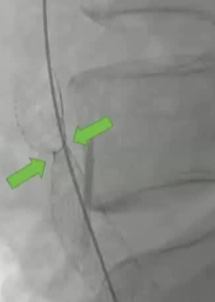

该病变先使用了一个直径为 14 毫米、压力为 20 大气压的球囊进行了 20 秒的预处理!

2. 如果没有血管内超声技术,预扩张则有助于实现支架尺寸的精确测量。【Oropallo 2023】【CIRSE SOP 2014】 3. 必须确保支架输送系统能够顺利通过并完成置入操作。【Oropallo 2023】【CIRSE SOP 2014】

其它考虑怎么做?How to do IT? 1. 建议将静脉段的扩张程度控制在与所选支架直径相匹配的范围内。【Rahmani 2023 Gibson 2022 Cirse SOP 2014 Raju 2013】 狭窄血管的过度扩张通常不会导致破裂,即便在慢性闭塞的情况下,血管也能承受较大的球囊扩张,并在随后置入较大的支架而不会发生破裂。 只有在以下情况才需例外处理:即在腹膜后区域或鞘管 环绕外科手术已经打开的静脉【joyce DP 2024】 对于慢性静脉阻塞的情况,采用逐渐增大直径的球囊进行多次扩张操作可能并非必要。 除非您无法将 14/16 毫米的气囊顺利穿过病变部位,否则可能需要进行多次扩张操作。【Barbati 2014】 2. 此外,该操作应贯穿整个病变部位的整个长度进行。【Oropailo 2023 Lichtenberg 2018】 ![]() 3. 使用高压球囊【Oropallo A 2023 Gibson 2022】 44岁 男 2次左髂股静脉血栓形成,以下静脉造影